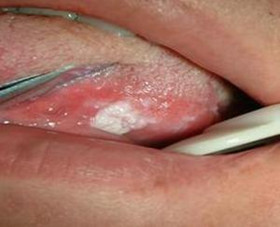

舌白斑多发生于舌背、舌腹或舌缘,白斑界限清楚,稍高于黏膜表面,颜色为乳白、灰白或微黄的白色。病损表面可粗糙不平或有颗粒增生,或呈疣状突起,或糜烂。也可在白斑中散布着一些发红区域。白斑可分为四种类型

4.糜烂型:白色斑块上有糜烂,可有溃疡形成。有明显疼痛。